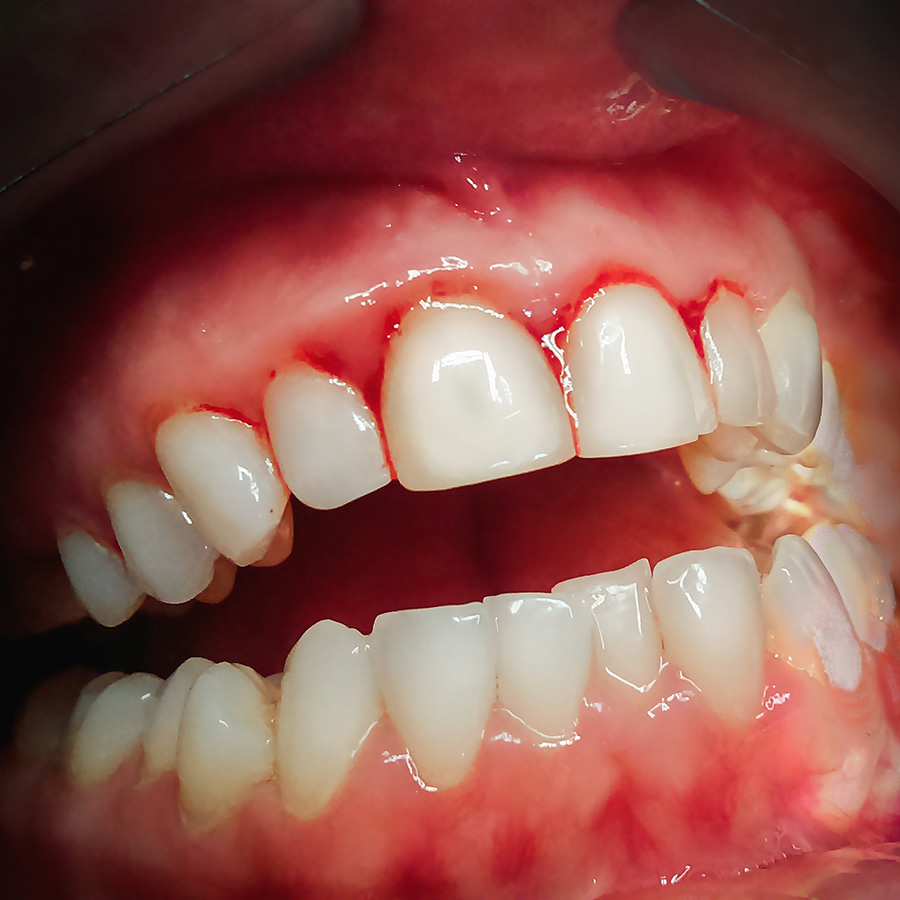

Gum disease is a common disease in adults. Three out of four adults develop it during their lifetime. Because it begins silently, many people don’t know they have it. However, the signs are there if you look and pay attention. Gingivitus causes inflammation of the gums. Its signs include: red or purple gums, tender or painful gums, gum bleeding (the number one cause of bleeding gums is gingivitis), and bad breath. Gingivitus happens when plaque builds up on teeth and inflames the surrounding gum tissue. If left untreated, gingivitis can lead to periodontitis, a much more serious gum disease that can result in tooth loss.